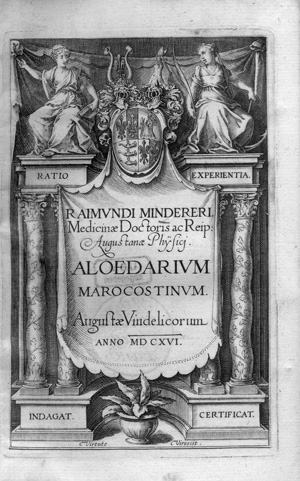

Minderer, Raimund

De Pestilentia liber unus. Veterum et neotericorum observatione constans

Nachverkaufspreis

400€ (US$ 455)